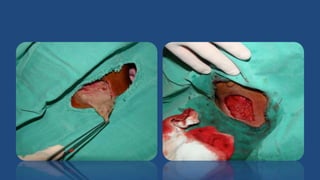

Drenagem Cirúrgica

• Tem por finalidade drenar

a secreção purulenta e

células necróticas

• Diminui a tensão dos

tecidos – alívio da dor

• Melhora o suprimento

sanguíneo local – facilita

o aporte de células de

defesa ao local

Inserção do Dreno

• Manter uma via de drenagem, evitando novo

acúmulo de secreção

• Estimula o aporte de células inflamatórias

para o local da infecção

• Não suturar oclusivamente as bordas da

incisão

• Remover em 48 a 72 horas (ou enquanto

tiver secreção)

Drenagem Cirúrgica • Tempor finalidade drenar a secreção purulenta e células necróticas • Diminui a tensão dos tecidos – alívio da dor • Melhora o suprimento sanguíneo local – facilita o aporte de células de defesa ao local

Inserção do Dreno •Manter uma via de drenagem, evitando novo acúmulo de secreção • Estimula o aporte de células inflamatórias para o local da infecção • Não suturar oclusivamente as bordas da incisão • Remover em 48 a 72 horas (ou enquanto tiver secreção)